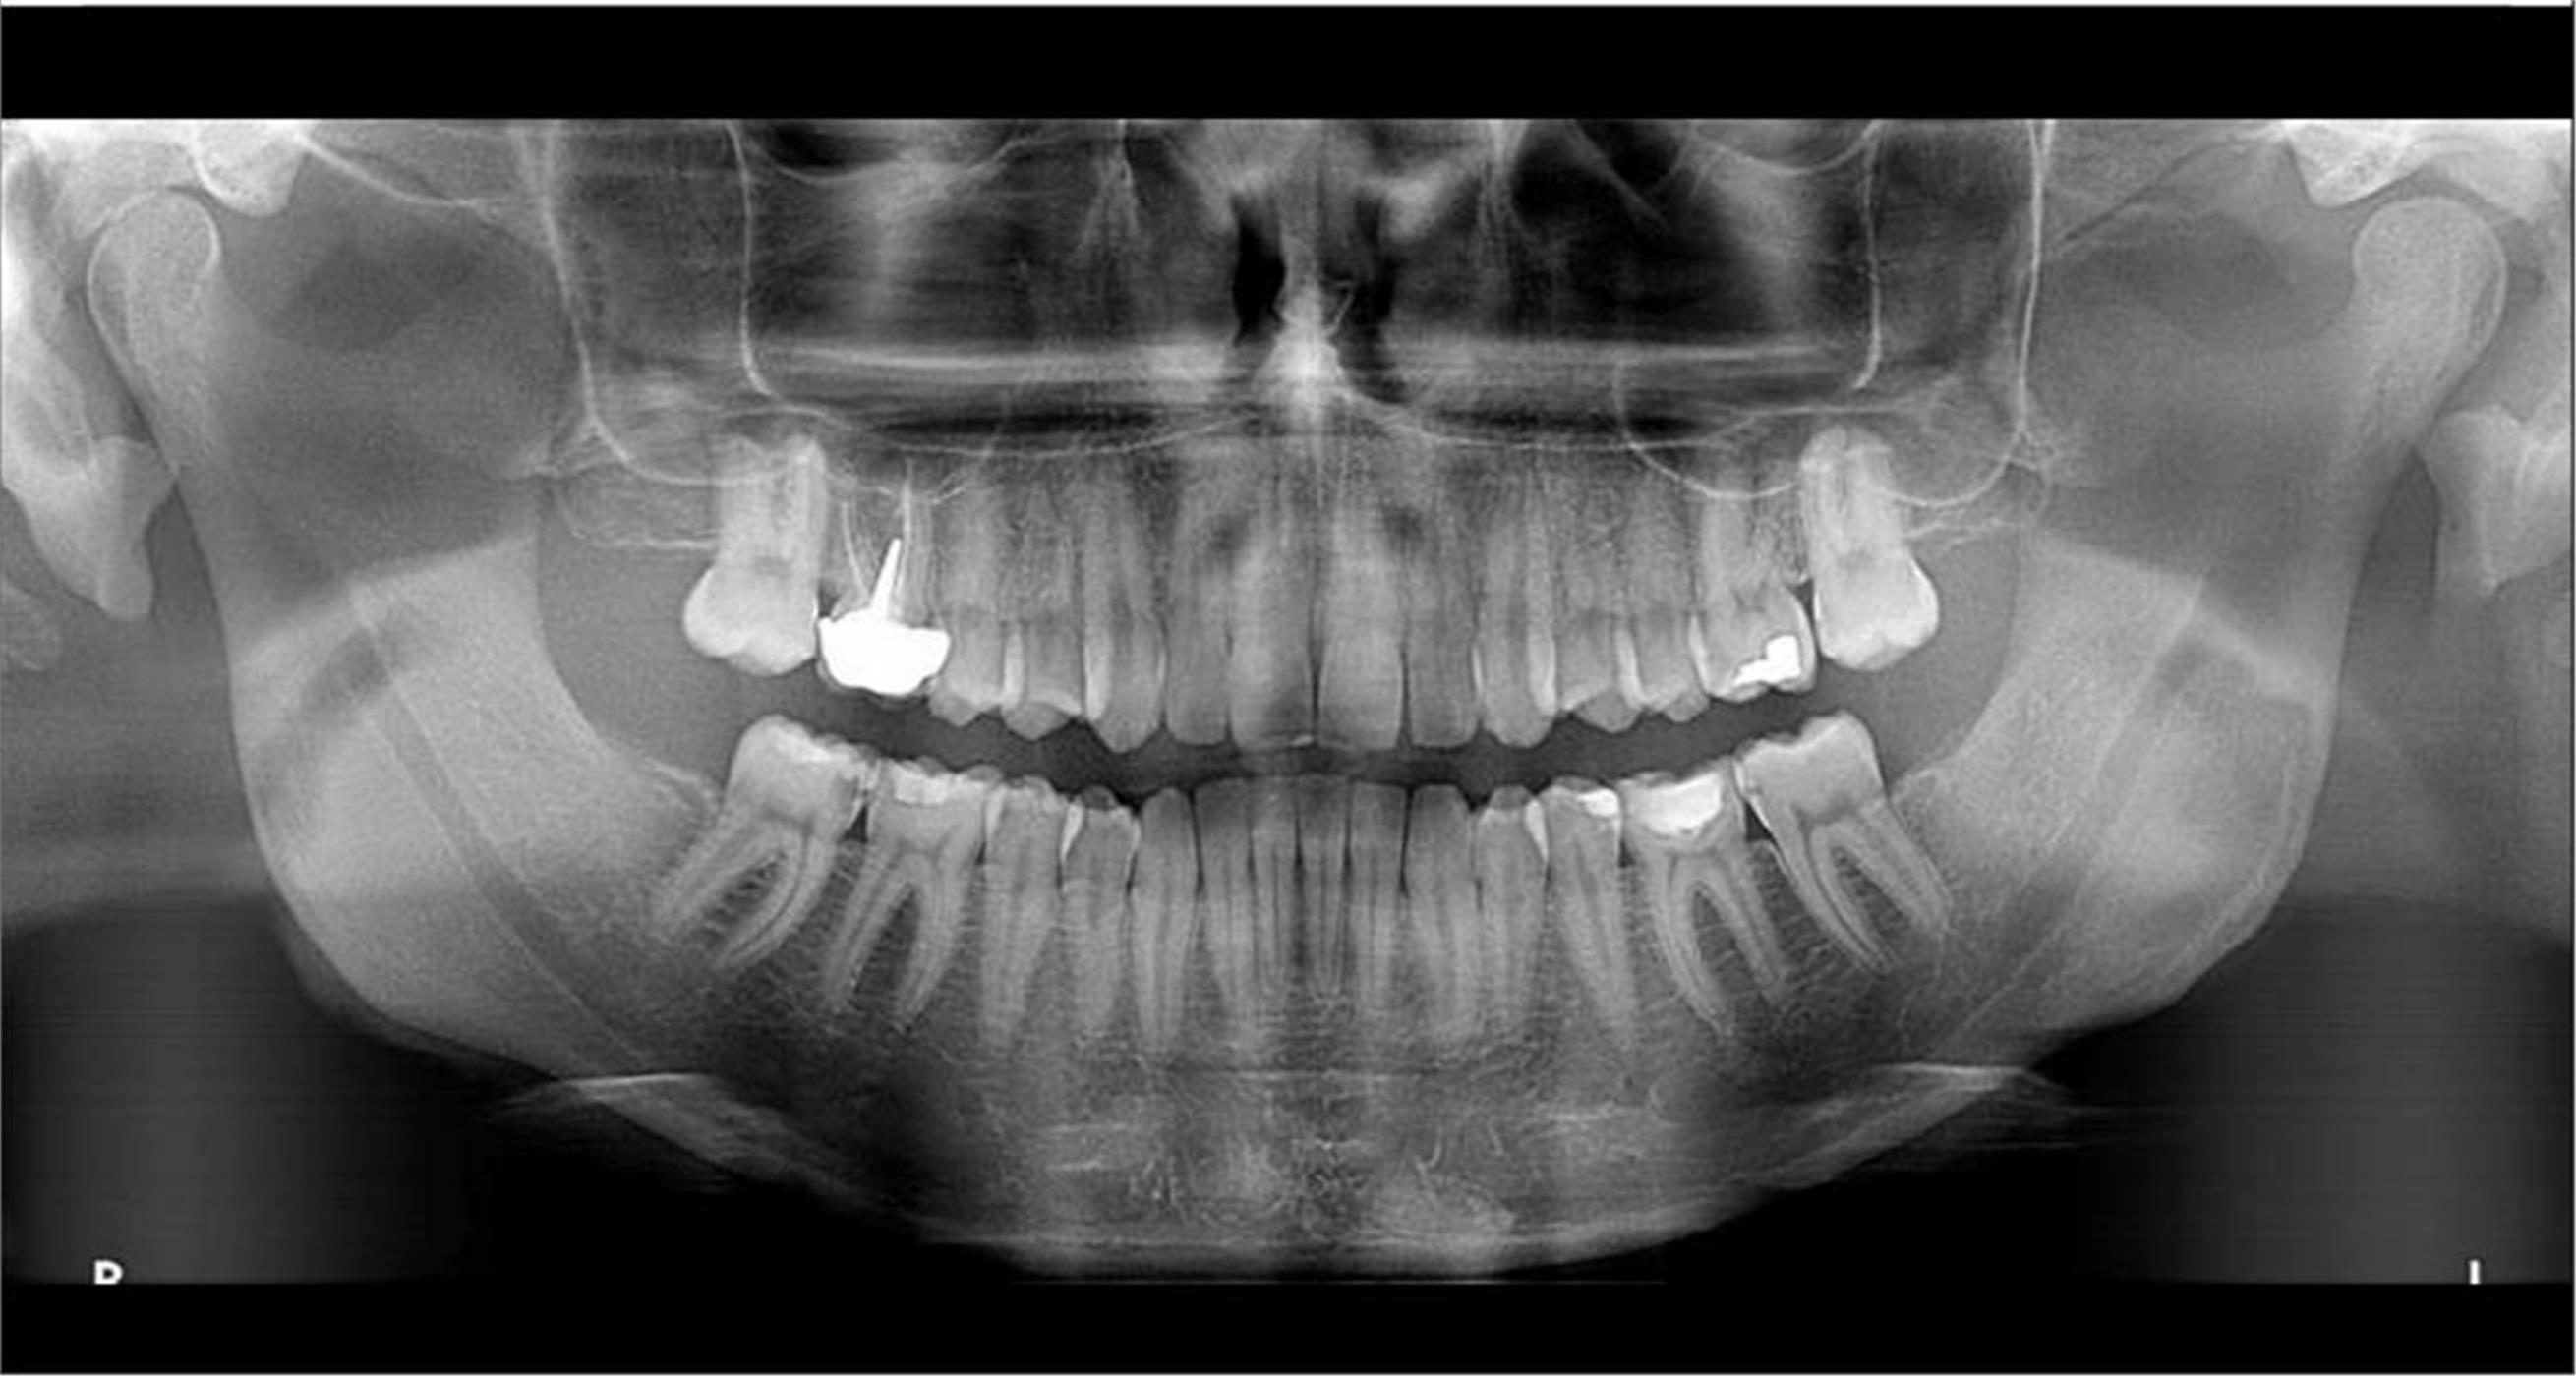

За само 13 секунди се добива високо квалитетна ортопантомграфска снимка, странична смнимка, снимка на вилични зглобови, снимка на синуси. Најновиот Kodak панорамикс има 2Д+ програма со која се добиваат 5 пресека во длабочина за прецизна дијагноза и позиција на импактирани заби и други промени. Со квалитетна панорамска снимка нашиот стручен тим ќе постави точна дијагноза и одреди соодветен план на терапија.